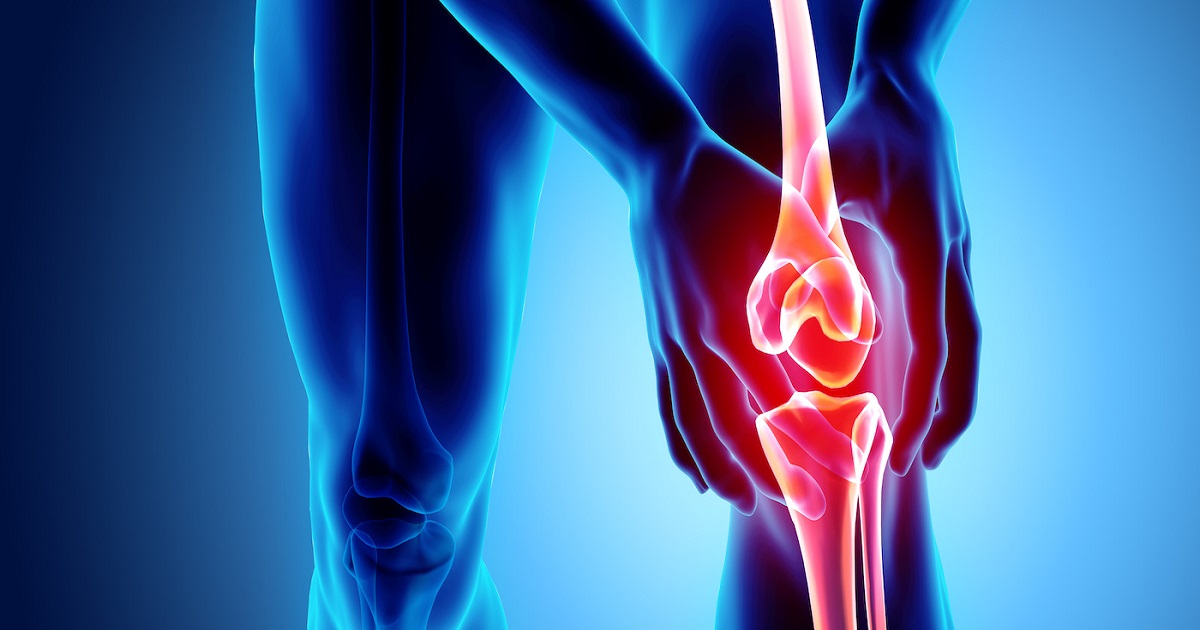

Намирници што не треба да ги јадете ако имате артритис

Артритисот е оштетување на зглобовите предизвикано од воспаление во телото. Ова е прилично честа патологија, а главниот симптом е силна болка. Но, правилната исхрана ќе ви помогне да го спречите напредувањето на болеста.

Со исфрлањето на храната што предизвикува проблеми, можете да го отстраните вишокот течности, да ја намалите тежината (што е дополнителен притисок на зглобовите) и да ги намалите воспаленијата и болката.

Прочитајте која храна треба да ја избегнувате ако имате артритис и болки во зглобовите.